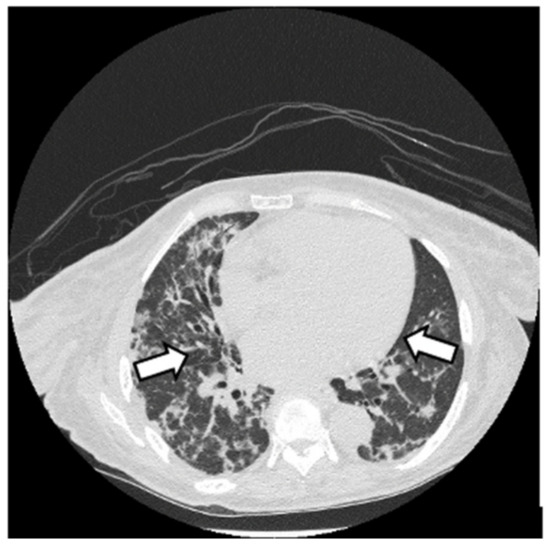

6.2. Histopathologic and Radiographic Findings in Myositis-Associated ILD